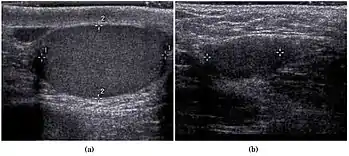

Scrotal ultrasonography of undescended testis: (a) Normal testis in the scrotum (b) Atrophic and decreased echogenicity of the contralateral testis of the same person seen in the inguinal region

In the minority of cases with bilaterally nonpalpable testes, further testing to locate the testes, assess their function, and exclude additional problems is often useful. Scrotal ultrasound or magnetic resonance imaging performed and interpreted by a radiologist can often locate the testes while confirming absence of a uterus. At ultrasound, the undescended testis usually appears small, less echogenic than the contralateral normal testis and usually located in the inguinal region. With color Doppler ultrasonography, the vascularity of the undescended testis is poor.